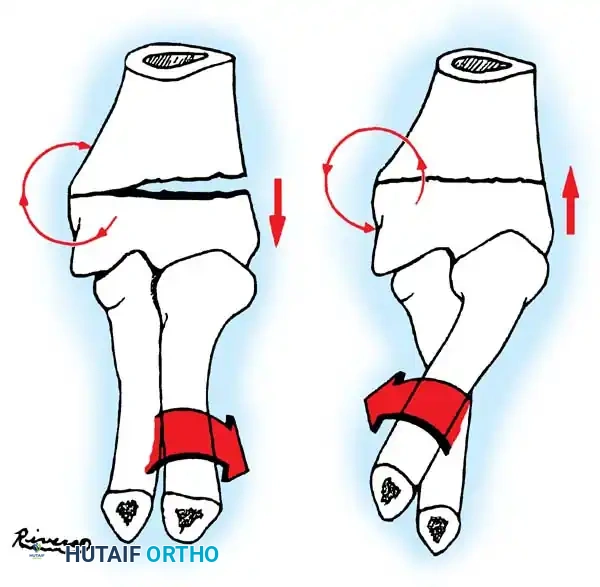

Fractures can present as angulated, translocated (shifted), or totally displaced. In the context of an elbow dislocation, the proximal fragment may become loose within the joint space or trapped, acting as a mechanical block to reduction.

Fig. 33-40 Examples of angulation, translocation, and total displacement of radial neck fractures.